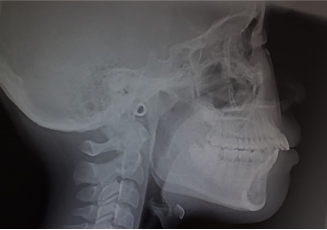

セファロ分析

セファロ分析は、頭部全体を撮影するレントゲンを使用し、矯正治療に不可欠な機器です。治療前の状態から経過を追いながら撮影を行うことで、矯正治療後の変化を確認することができます。撮影を通じて、上下の顎の大きさや形、ずれ、歯の傾斜角度や口元のバランスを把握し、そこから最適な治療計画を立てます。